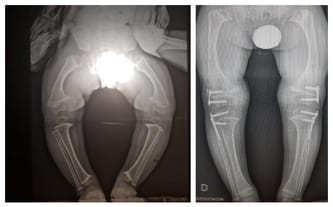

dzięki Waszemu wsparciu Jurek przeszedł poważną operację bioder, która trwała około 5 godzin. Zostały mu założone płytki, dzięki którym dr Paley mógł ustawić biodra w prawidłowej pozycji.

Pasaron los meses y no nos dimos por vencidos. Finalmente, enviamos la documentación al Dr. Paley y él fue el primero en diagnosticar una enfermedad que finalmente fue confirmada por pruebas genéticas. Displasia ... Una palabra difícil, pero para averiguar qué le pasa a Jurek, simplemente hay que ver sus fotografías. Las piernas arqueadas hacian que mi hijo se caiga cada pocos pasos y, además, afectaba a una posición incorrecta de la columna vertebral. Jurek veia a sus compañeros sanos y trataba de imitarlos, lo que generalmente terminaba en llanto, muchos chichones y moretones. En enero 2019 pudimos recaudar el dinero para la operacion de rodillas que gracias a ella Jurek ahora tiene las piernas rectas . Ahora necesita una cirugia de cadera.